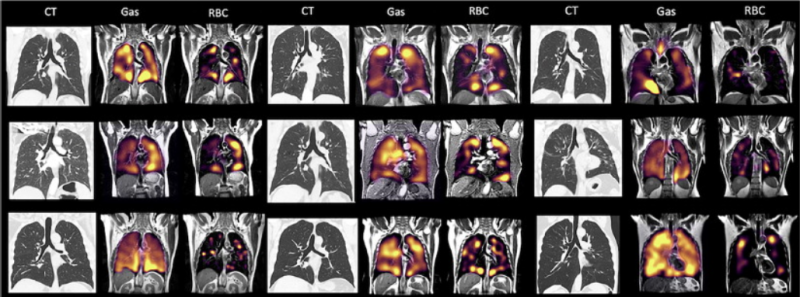

This photo gallery shows the variety of radiological presentations of COVID-19 (SARS-CoV-2) in medical imaging, including computed tomography (CT), radiograph X-rays, ultrasound, echocardiograms and magnetic resonance imaging (MRI). The radiology images show examples of typical COVID pneumonia in the lungs and the numerous complications the virus causes in the body in multiple organs, including the brain, kidneys, heart, abdomen and vascular system.